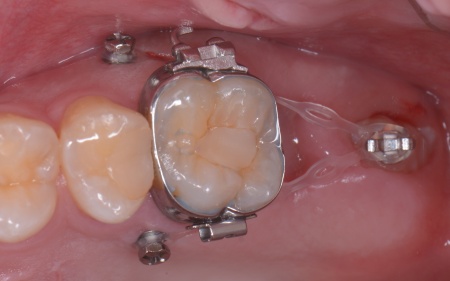

続いて歯茎に矯正用インプラントと呼ばれるネジを打ち込み、これと隣の歯を固定源としながら、埋まっている親知らずを矯正の力で引っ張りだしました。

矯正治療により、親知らずが歯並びのラインに収まってきたところで、歯根の先端を手前側に起こす力を与えるためにワイヤーをかけ、歯を移動させながら歯列が平行になるように調整します。